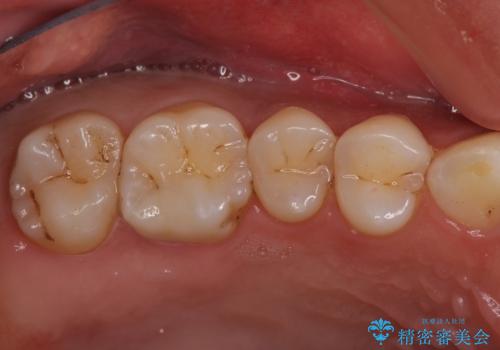

今回は虫歯が大きかったものの、ぎりぎり神経に達しておらず、セラミックインレー(つめもの)の治療のみで完了しました。初診時に虫歯を除去し、後日神経のテストをして正常反応を確認しました。

虫歯を徹底的に除去し、なおかつ神経に達しているかを慎重に判断するには、どうしても顕微鏡&長時間の診療が必要になりますが、保険外治療となります。

自分の歯や神経をなるべく残すには保険外治療をおすすめしています。